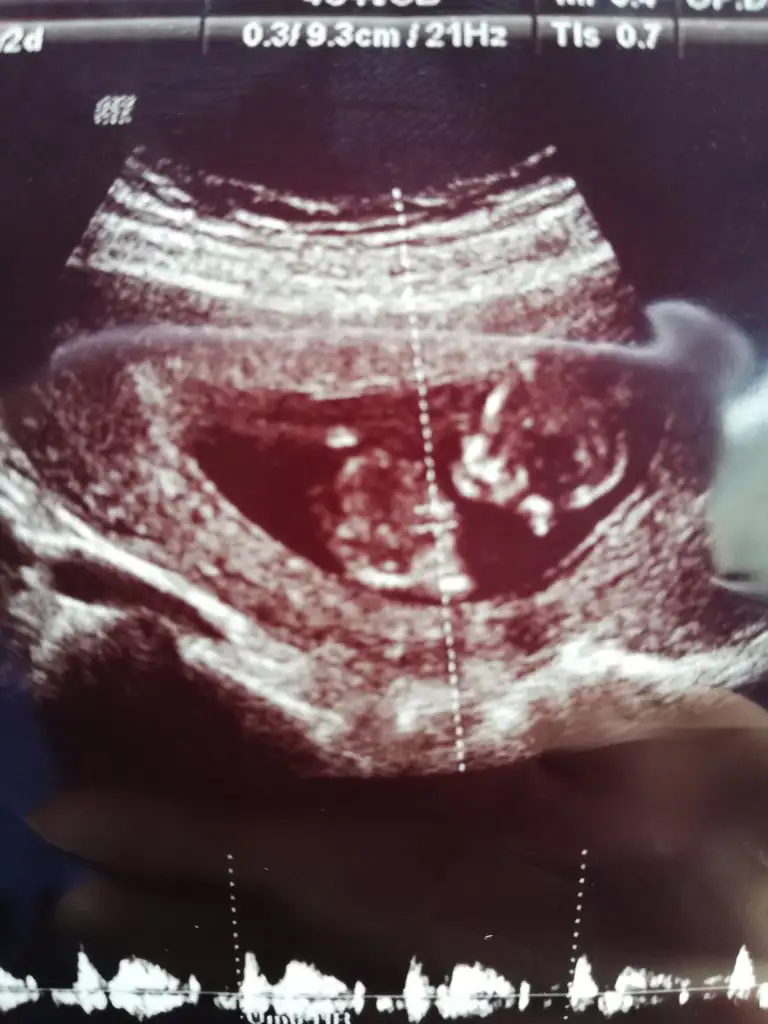

Hanımlar benim bebeğime de yorum yapabilecek biri var mı?? Çok merak ediyorum. Doktor bir tahminde bulundu ama sizler ne söylüceksiniz merak ediyorum :KK54:

Erkek mi dedi doktorunuz

Evet doktorum çok küçük ama erkek gibi, kesin olarak bir sonraki muayenede belli olur dedi :) teşekkür ederim siz erkek mi diyorsunuz ^_^

12+5 usg ne zaman tahmin etti dr nuz 131 haftadasınız saglıkla gelsin minnoşunuz

Bu ultrasonun çekildiği gün söyledi yani tam 12+6 iken tahmin etti, kesin değil sadece erkek gibi dedi.